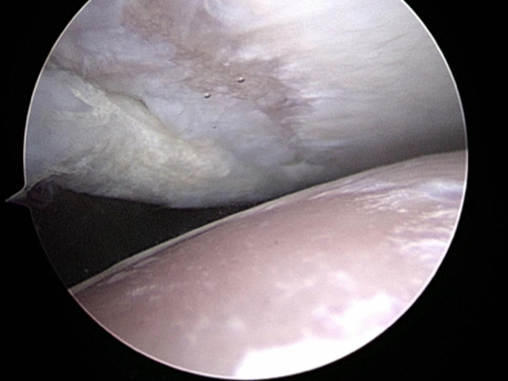

- Supraspinatus Insertionopathy is a poorly understood condition. The supraspinatus muscle attaches onto the humerus directly over the biceps insertion within the joint. In some patients damage to the attachment fails to heal and the attachment site degenerates, this can lead to mineralization within the attachment. The mineralization is the tip of the iceberg. This insertionopathy itself can be painful but it can also cause impingement of the biceps tendon. Treatment is by debriding the impingement or releasing the biceps tendon and using platelet right plasma (PRP) and sometimes stem cells to stimulate healing and reduce inflammation. These cases will typically take a long time to resolve and avoiding reinjury is vital.

- Caudal shoulder instability syndrome is a condition that we are just starting to appreciate. The shoulder is a joint that will often tolerate considerable injury and when the cause of that injury is a repetitive strain little on little build up occurs over time. In this condition which we have recognised and we are starting to build up a better understanding of, damage to one or more of the supporting structures but primarily the biceps tendon leads to a front to back micro instability. This in turn leads to the humeral head impacting onto the caudal glenoid rim and eventually a fragment breaks off in this site. Removal of the fragment can sometimes help but there is often considerable damage already inside the shoulder with full thickness loss of cartilage. In these cases vigorous physiotherapy, shoulder support braces, oral pain killers and biologic treatments are used to try and improve things however the prognosis may not be good and this does seem to depend heavily on the extent of cartilage loss

- Osteocondritis Dissecans (OCD). This is a condition in young large breed dogs and results in a flap of cartilage and bone coming free from the back of the humerus. Removal of this flap by arthroscopy or arthrotomy will help settle the problem but there will always be a defect in the joint surface. In most cases this is not a clinical problem but in some where the defect is very large it can be a problem. In cases that have large lesions seen on CT we may suggest resurfacing with a synthetic plug inserted in to the OCD lesion. This is called a SynACART and does require a fairly large exposure and open surgery.